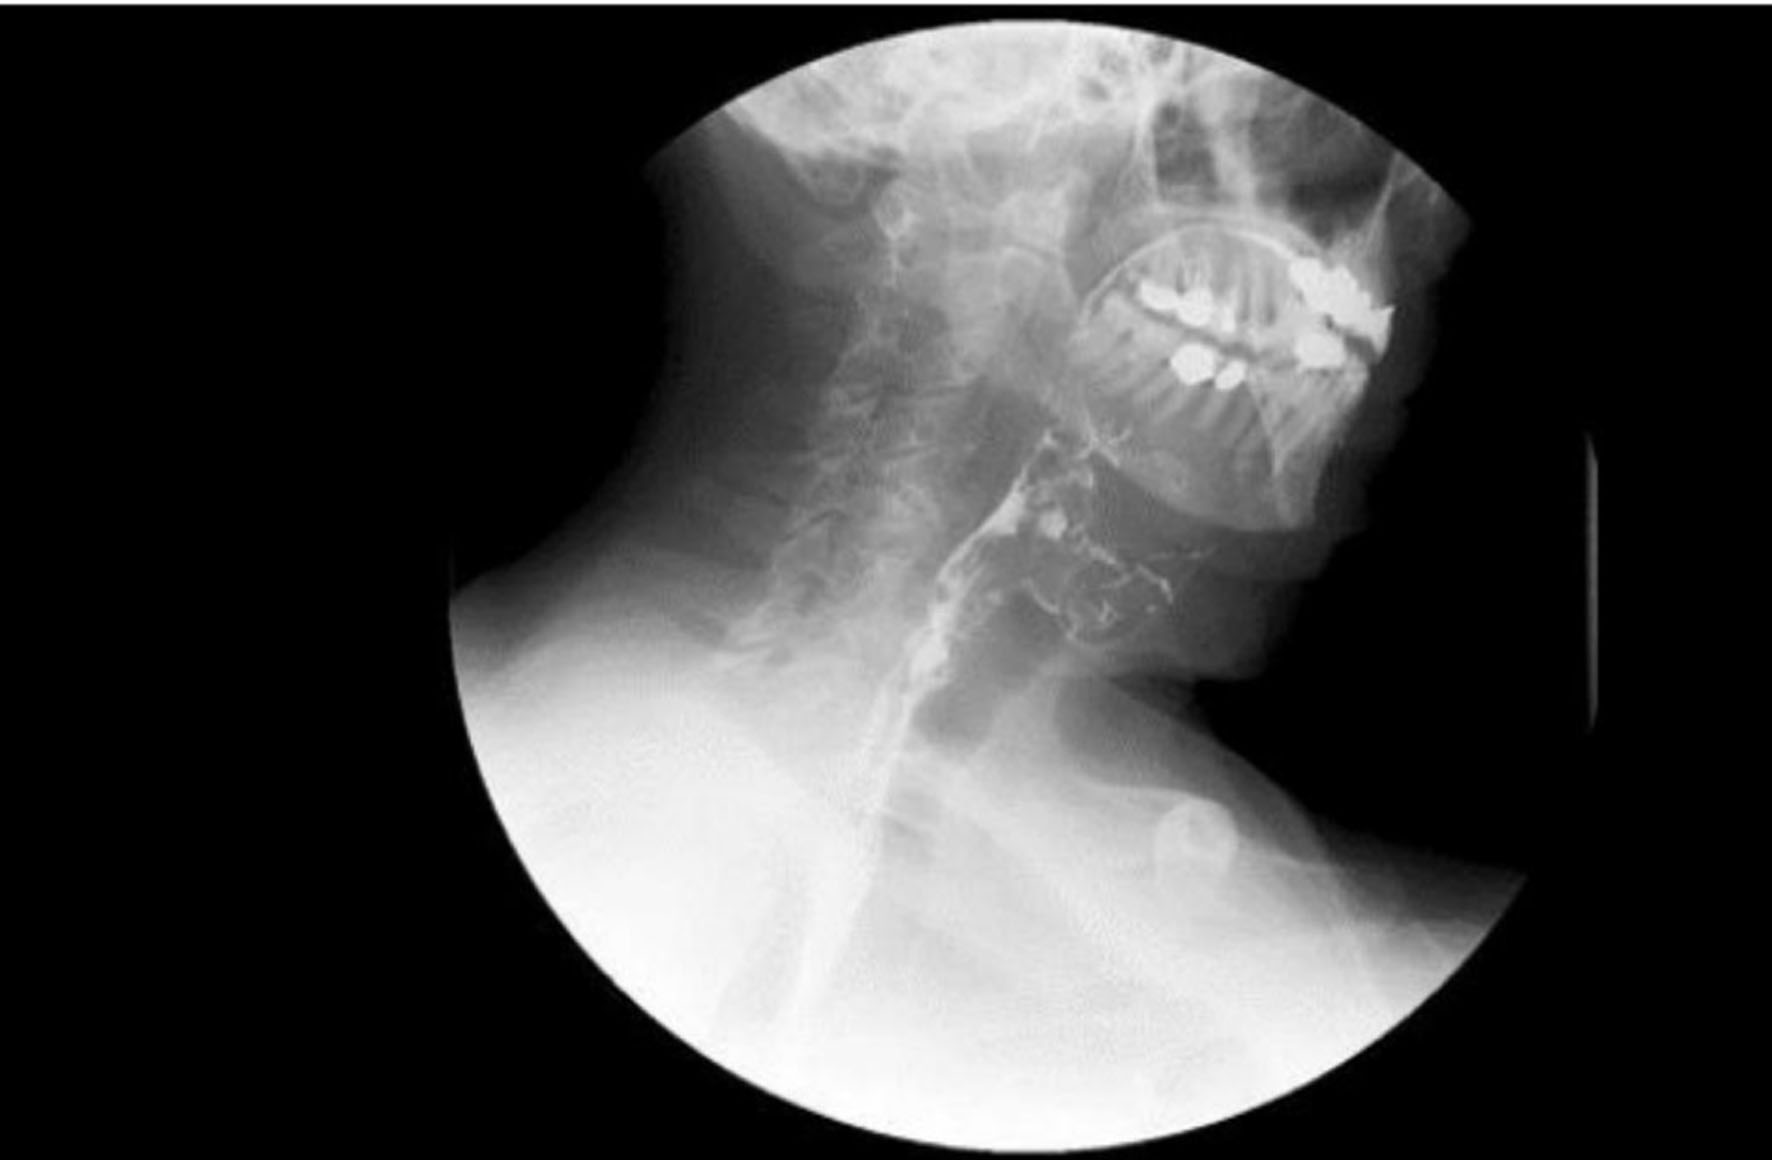

After 6 more months of persistent dysphagia and weight loss without a diagnosis, the patient presented to our network for further workup and treatment recommendations. CT of the neck 12 months postoperatively showed anterior cervical plate in adequate position with air between the plate and esophagus (Fig. 2). An upper endoscopy was performed at 12 months postoperatively, which showed fistulization between the esophagus and the metal hardware in the cervical spine. An esophagram was also performed, which demonstrated no obstruction but decreased peristalsis of the lower esophagus and lateral rightward deviation of the left upper cervical esophagus with minimal mucosal irregularities. Esophagram also showed involvement of the posterior wall of the cervical esophagus overlying the anterior plate and screws without evidence of leak or fistula (Fig. 3).

![]() Click for large image | Figure 3. Esophagram at 12 months. Red arrow indicates defect. The image shows contiguity between the lumen of the esophagus and the cervical hardware based on the transit of the oral contrast, consistent with a posterior esophageal wall perforation contained by the cervical hardware without extravasation. |